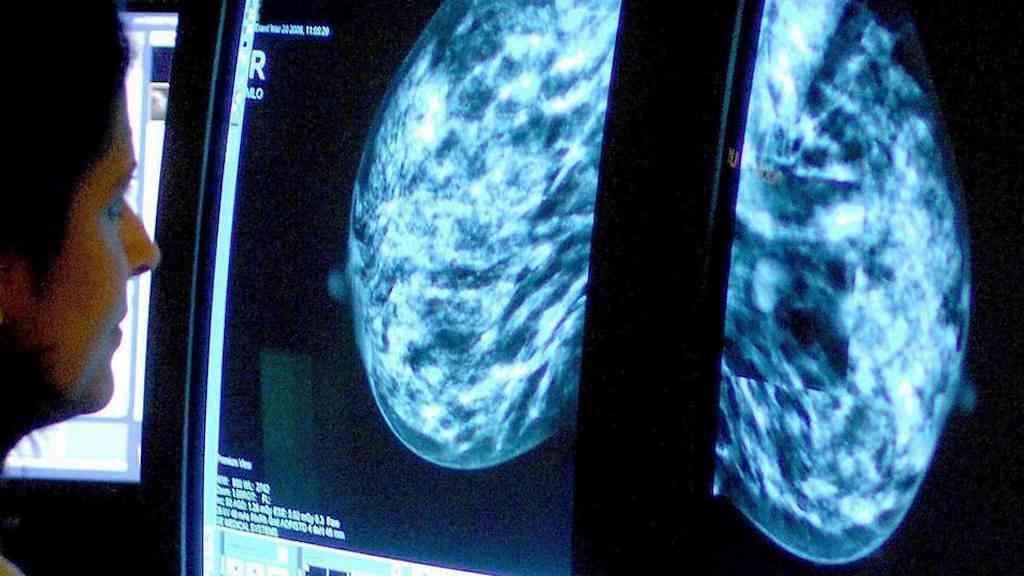

Os tipos de câncer mais letais são o de mama, traqueia, pulmão, intestino e estômago. Entre esses, o câncer de mama foi o mais frequente entre os pacientes nos últimos 30 anos.